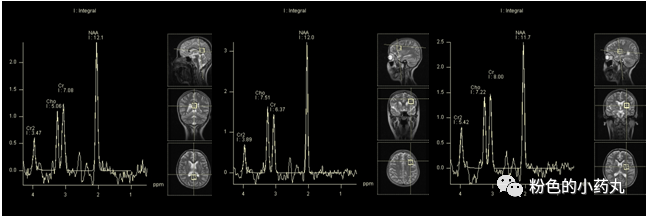

MRS:急性期可出现Lac峰增高(无特异性,缺血,感染,炎症及肿瘤也可引起乳酸增高),Cho峰升高和NAA峰减低。

图 病例3

MRS可见乳酸峰